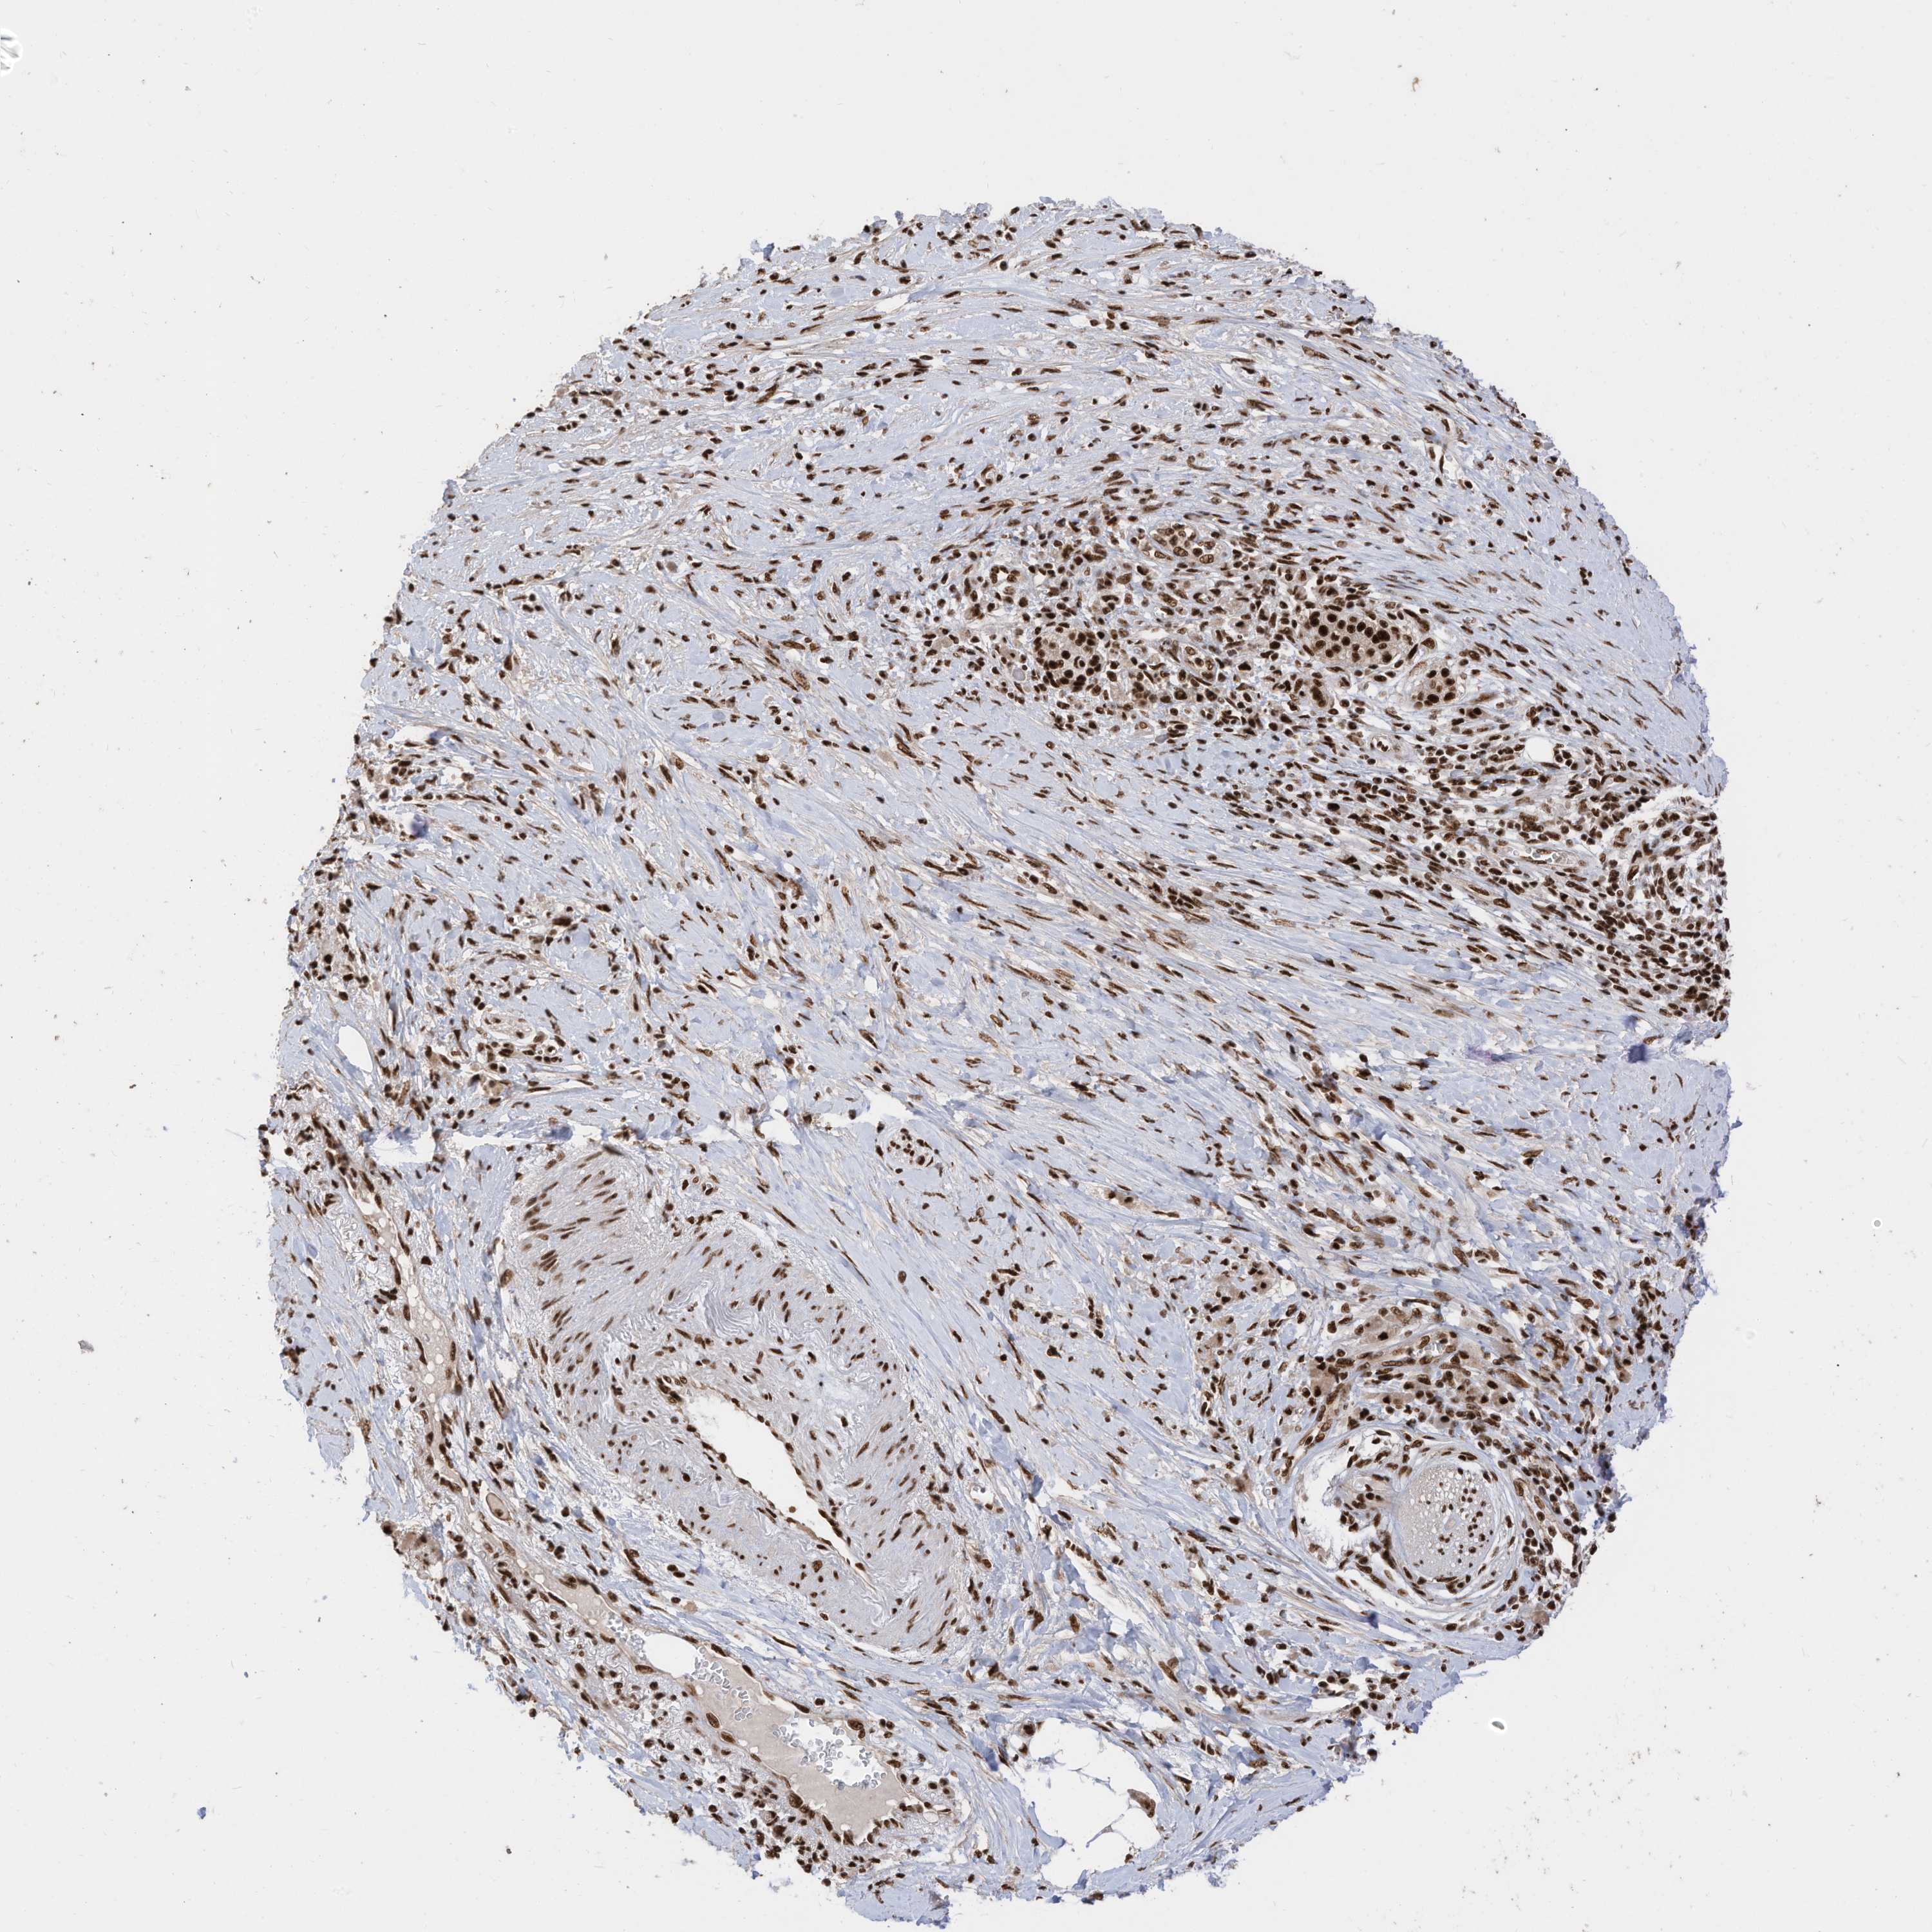

PANCREATIC CANCER - Protein expressioni

A mouse-over function shows sample information and annotation data. Click on an image to view it in a full screen mode. Samples can be filtered based on level of antibody staining by selecting one or several of the following categories: high, medium, low and not detected. The assay and annotation is described here.

Note that samples used for immunohistochemistry by the Human Protein Atlas do not correspond to samples in the TCGA dataset.

Antibody stainingi

Antibody staining in the annotated cell types in the current human tissue is reported as not detected, low, medium, or high, based on conventional immunohistochemistry profiling in selected tissues. This score is based on the combination of the staining intensity and fraction of stained cells.

Each image is clickable and will lead to virtual microscopy that enables deeper exploration of all samples and also displays staining intensity scores, fraction scores and subcellular localization as well as patient and tissue information for each sample.

Antibody HPA032054

Antibody HPA032055

Staining

Nuclear

Adenocarcinoma, NOS